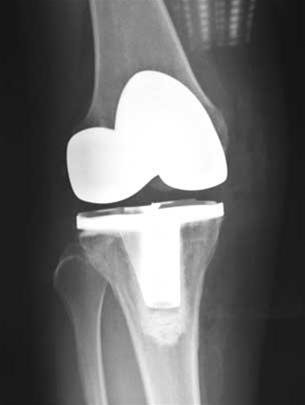

| Khớp gối nhân tạo đã thay |

Biện pháp cuối cùng khi sụn hư hoàn toàn là thay khớp gối nhân tạo toàn phần. Cũng theo số liệu nghiên cứu trên 35 bệnh nhân đã được thay khớp gối toàn phần tại Bệnh viện ĐHYD thì có bốn bệnh nhân được thay cả hai bên. 32 bệnh nhân có kết quả tốt và rất tốt, đi lại hết đau, ba ca có kết quả trung bình rơi vào những bệnh nhân bị thoái hóa khớp do viêm đa khớp.